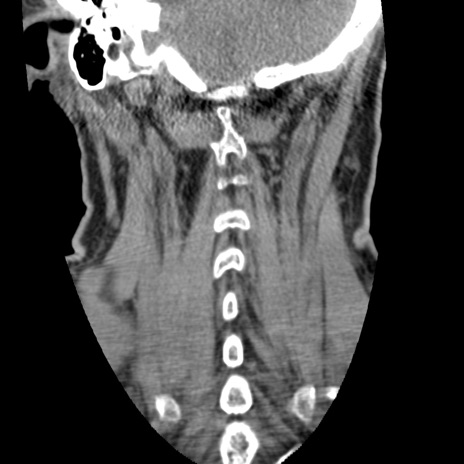

症例50 頚椎CT(冠状断像)

【症例】60歳代女性

【主訴】後頭部〜右後頸部にかけての痛み

【現病歴】本日飲食店でコーヒーを飲んでいたところ、突然後頭部〜右後頸部にかけて痛みが出現し、右上肢の感覚障害を伴ったため救急要請。

【身体所見】脳神経学的に明らかな異常所見を認めず。右上肢に軽度の感覚障害あり。

異常所見と診断は?